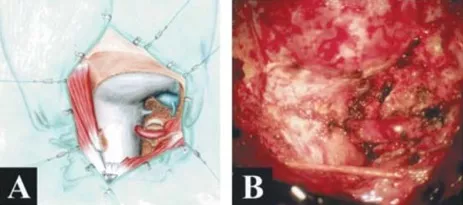

巴教授采取了左侧卧位远外侧入路全切肿瘤,让Belle置于左侧侧位,头部轻微弯曲并旋转到右侧。手术术中应用躯体感觉和听觉诱发电位的连续监测。枕下旁侧骨瓣开颅延伸至远侧乙状窦、C1半椎板切除术,枕骨大孔的背外侧边缘逐渐被魔钻磨除,术中并对脑干和脊髓进行了精心保护。

术中及肿瘤切除后的硬膜内部位

手术切口及手术时病人的位置